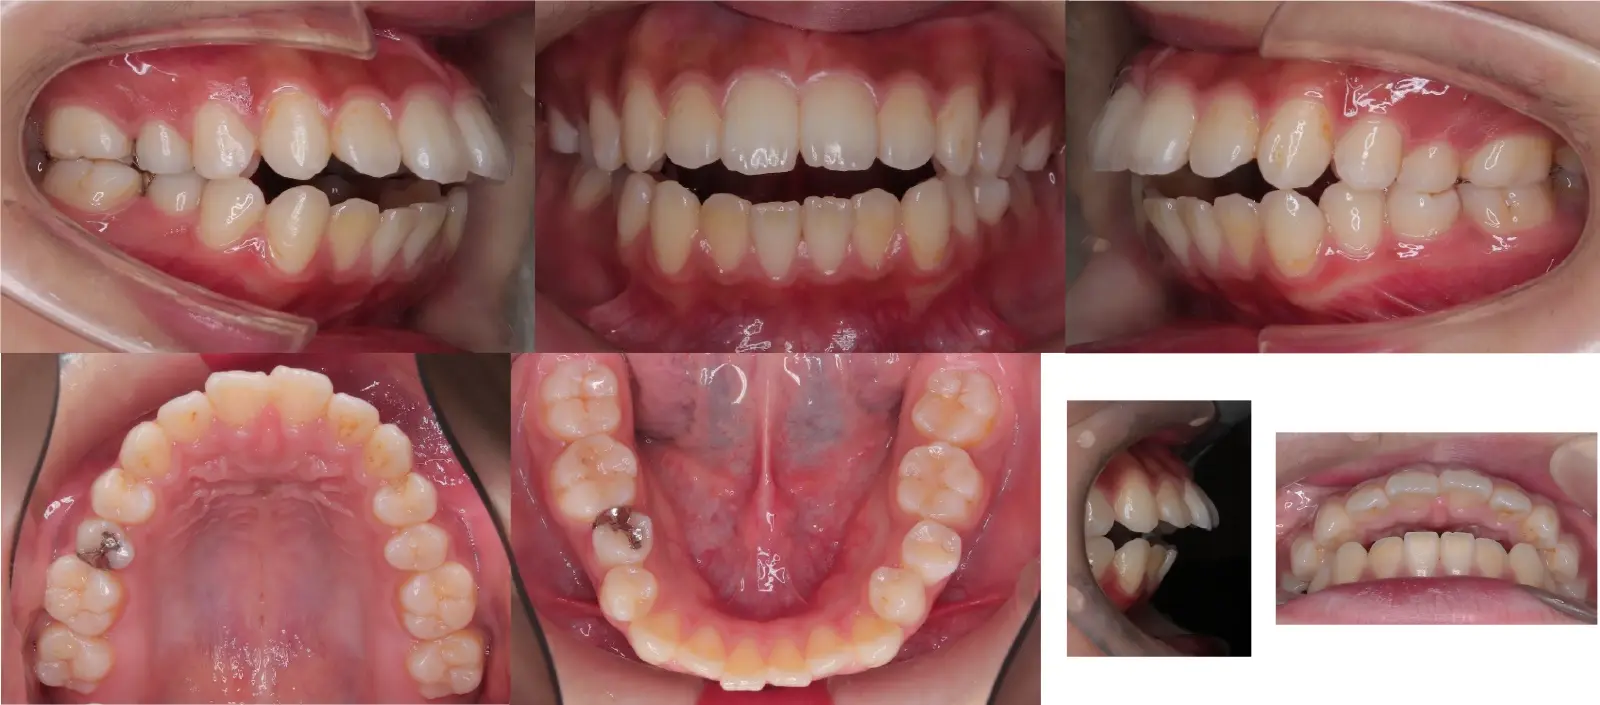

アングルⅡ級叢生を伴う上顎前突症

- 主訴

出っ歯

- 年齢

20代

- 治療期間

2年6ヶ月

- 治療回数

29回

- 治療に用いた主な装置

カスタムメイド型リンガルブラケット矯正装置 (WIN)

- 治療費

1,400,000円(税別)トータル料金

- 抜歯部位

上顎の中切歯が失活歯で、根尖病変が存在したため、上顎中切歯と下顎左右側第一小臼歯を抜歯。